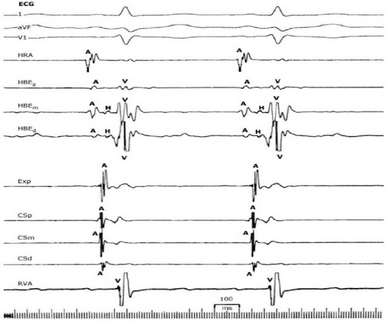

Em relação ao eletrograma abaixo. é correto afirmar que:

Legenda: 1= derivação DI; aVF e V1 = derivações do eletrocardiograma; HRA = derivação atrial alta; HBE = eletrodo no sistema His (p = proximal; m = médio; d = distal); Exp = eletrodo exploratório; CS = eletrodo no seio coronário (p = proximal; m = médio; d = distal); RVA = eletrodo no ventrículo direito; A = registro atrial; H = registro em His; V = registro ventricular.